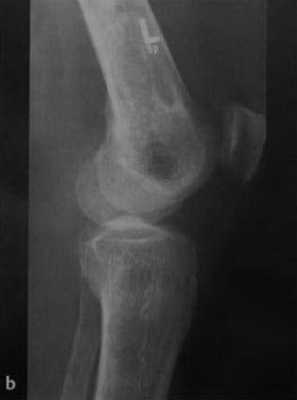

b) Рентгенологическое исследование демонстрирует выраженный склеротический край и центральный участок снижения рентгенопрозрачности в дистальном отделе бедренной кости и в большеберцовой кости. Проксимальный отдел бедренной кости демонстрирует участок частичного грубого склероза, который иногда трудно отличить от энхондромы.